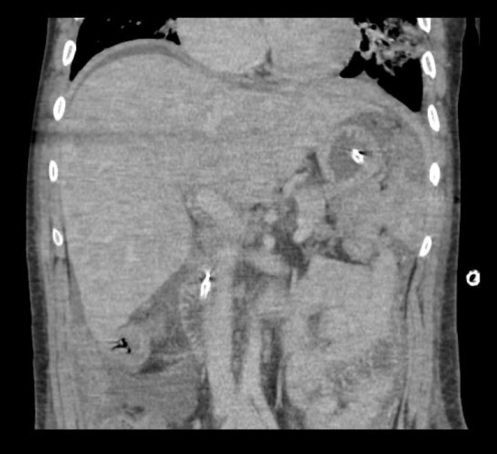

Abstract: We report a case of a 34 year old male with AIDS who presented to the hospital with abdominal pain and dyspnea. He received a comprehensive work-up including extensive imaging and biopsies revealing high grade mature B-cell lymphoma with features consistent with Burkitt’s Lymphoma with concomitant Ebstein Barr viremia. This case demonstrates the need for vigilance when assessing patients with HIV or AIDS for lymphoma with vague complaints and no identifiable source of infection.References